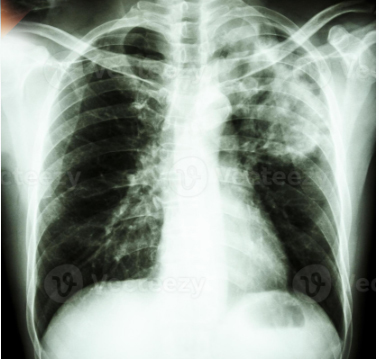

La radiografía de tórax de la película muestra un infiltrado alveolar en la parte superior del pulmón izquierdo debido a una infección por Mycobacterium tuberculosis tuberculosis pulmonar.